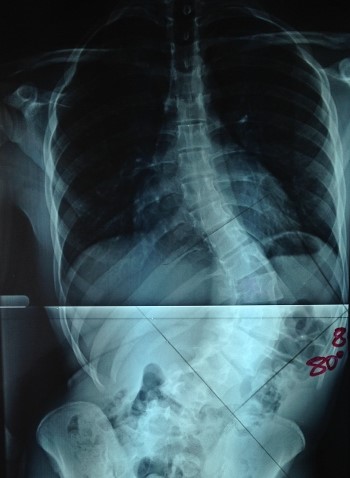

Upload Date: March 31, 2019 Full Size Image Dimensions: 350 × 478 Image Parent Post: ΧΕΙΡΟΥΡΓΙΚΗ ΣΠΟΝΔΥΛΙΚΗΣ ΣΤΗΛΗΣ

1.Προεγχειρητική εικόνα οσφυικής σκολίωσης